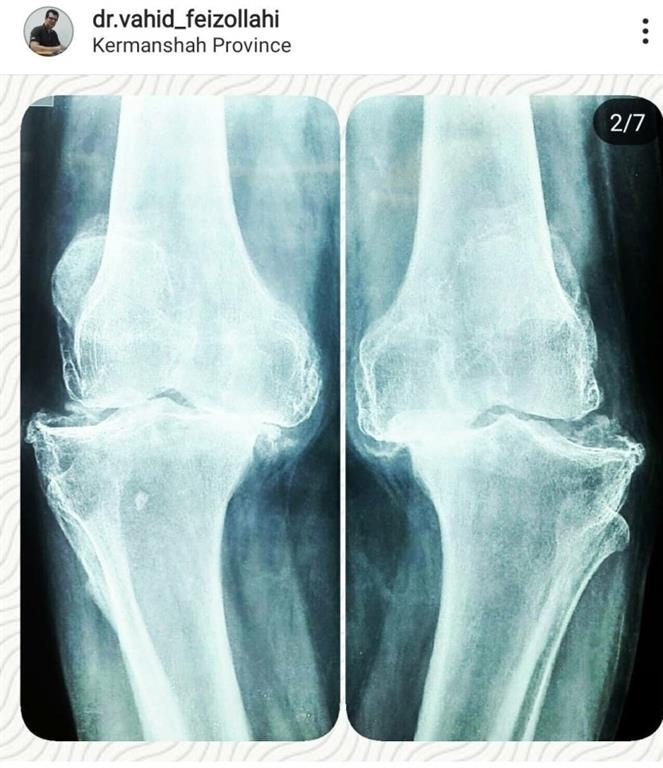

1. A 70-year-old woman

The patient was a 70-year-old woman with severe osteoarthritis that lead to her inability to stand up and walking and movements and knee deformity , which was performed simultaneously with bilateral knee replacement of the right and left knees, and was started by the patient's walker the day after surgery.